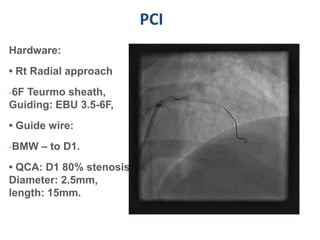

PCI

Hardware:

• Rt Radial approach

-6F Teurmo sheath,

Guiding: EBU 3.5-6F,

• Guide wire:

-BMW – to D1.

• QCA: D1 80% stenosis,

Diameter: 2.5mm,

length: 15mm.